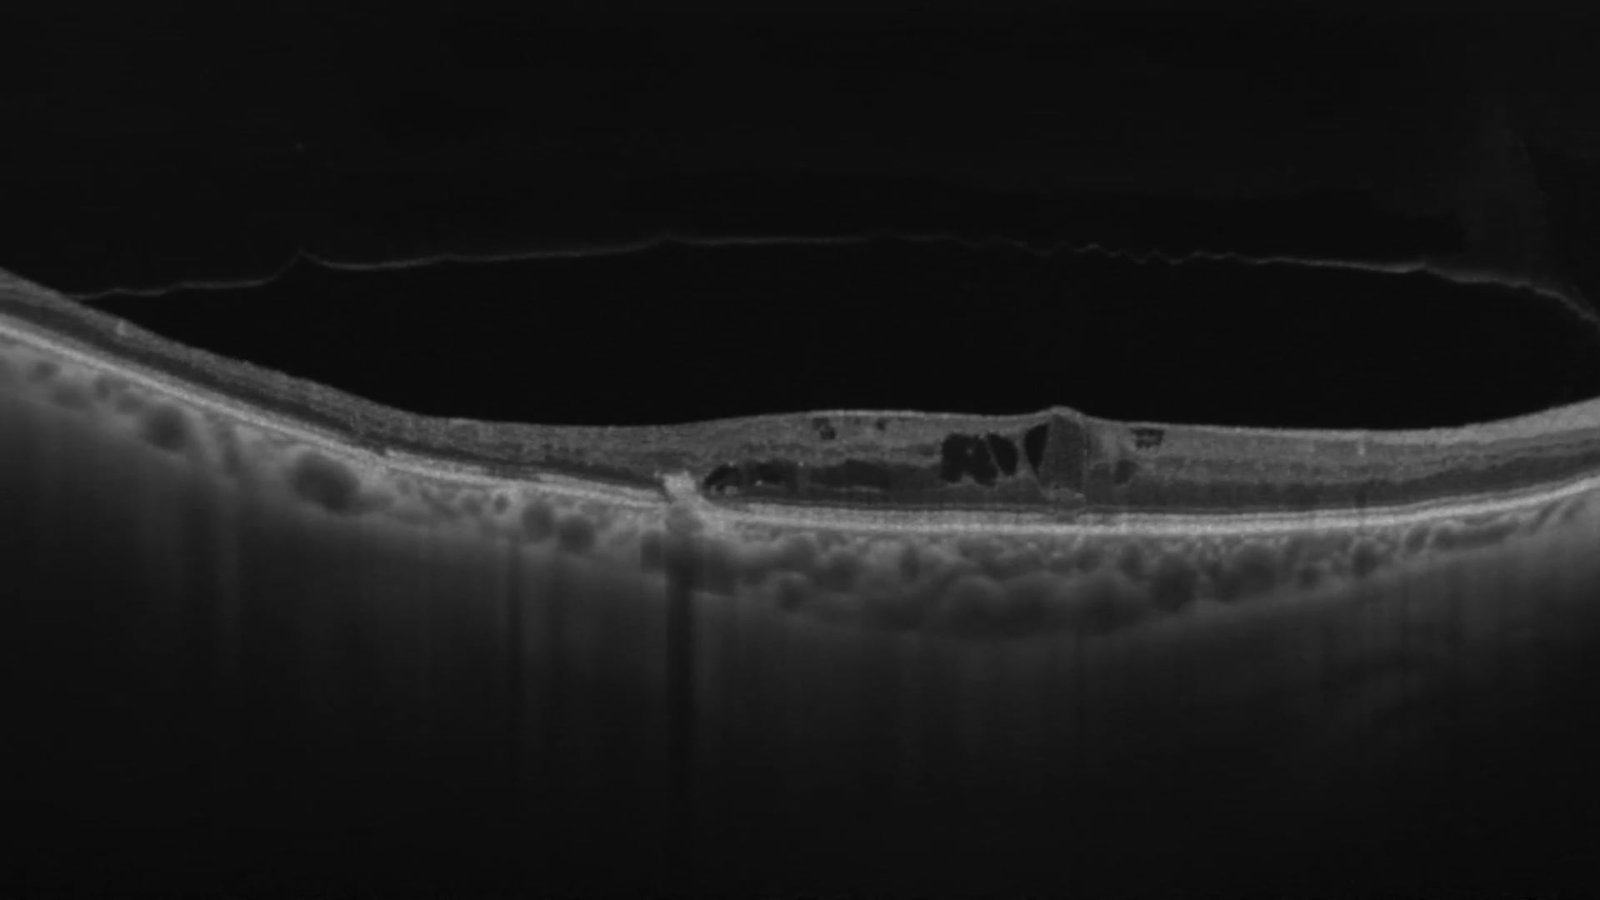

ReDMEK

Asistencia de OCT intraoperatorio para realizacion de ReDMEK